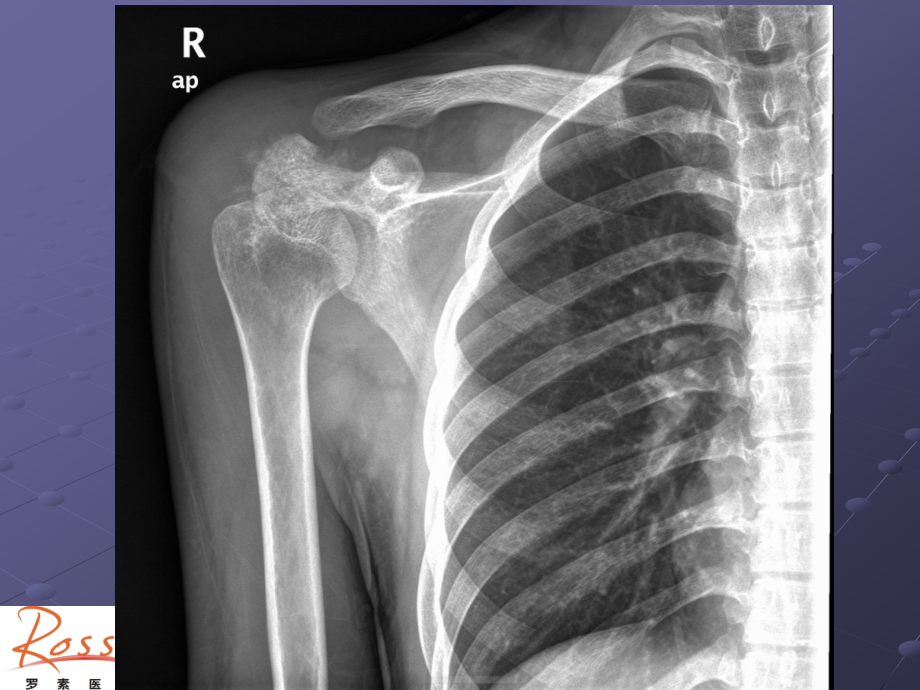

,*,单击此处编辑母版文本样式,第二级,第三级,第四级,第五级,单击此处编辑母版标题样式,病例,男,,20,岁,一周前打球右肩外伤。现红肿,高热,抗炎效果不佳。,?,肩胛骨尤文氏肉瘤,尤文氏肉瘤,尤文氏肉瘤起源于骨髓间充质性结缔组织是由含糖原的特殊小圆形细胞所组成,与其他起源于骨髓的小圆形细胞肿瘤的鉴别主要依靠免疫组织化学检查。尤文氏肉瘤约占骨恶性肿瘤的,4,6%,,男性略多于女性,多见于,5,30,岁,,90,发生于,30,岁之前,尤文氏肉瘤发病年龄小者多位于管状骨,,20,岁以上发病者多发生于扁骨。发生于下肢及骨盆者共占,2,3,。疼痛为主要症状,初为间歇性隐痛,迅速转为持续性剧痛,本病发展快,病程短,早期即可广泛转移,预后不良。,肿瘤生长特征,1.,肿瘤由骨髓腔向骨皮质发展,骨松质和骨皮质溶解破坏;,2.,侵袭骨膜可产生不同程度的反应;,3.,突向周围形成较明显软组织肿块;,4.,肿瘤为非成骨性,故不形成肿瘤性骨组织或软骨组织。,CT,表现,1.,溶骨性破坏:骨髓腔呈梭形膨胀,发生于扁骨的少有膨胀;骨皮质可硬化增厚或被破坏变薄呈虫蚀状。,2.,骨膜反应:呈放射状、葱皮样及,Codman,三角改变。发生扁骨的骨膜反应较轻。,3.,软组织肿块:其内常出现出血、坏死瘤周伴有水肿。,本例特点及鉴别,特点:,20,岁青年男性;右肩胛骨肩峰骨皮质硬化增厚,并见边缘虫蚀样骨质破坏,无膨胀性改变,未见肿瘤骨;有较明显的骨膜反应;周围可见软组织肿胀。,鉴别:主要和骨肉瘤鉴别,肿瘤骨为其特征性表现,软组织肿块多包绕骨端。,骨肉瘤,骨肉瘤是指瘤细胞能直接形成骨样组织或骨质的恶性肿瘤。,男女发病之比约,1.7:1,,好发年龄为,11,30,岁。最常发生于股骨,胫骨次之,其余依次为肱骨、颌骨、腓骨及骨盆。,骨肉瘤的恶性程度高、进展快,多早期发生肺转移,是最常见的原发性恶性骨肿瘤,发病率约占骨恶性肿瘤的,34%,。,疼痛、局部肿胀和运动障碍是骨肉瘤三大主要症状。,影像学表现,1.,骨质破坏:多始于干骺端中央或边缘部分,骨松质斑片状骨破坏,皮质边缘虫噬样破坏,在皮质内表现为哈弗氏管扩张而呈筛孔状破坏,后期骨破坏区形成大片骨缺损。,2.,肿瘤骨:骨破坏区和软组织肿块内的肿瘤骨是本病本质的表现,也是影像诊断的重要依据。肿瘤骨的形态主要有:云絮状斑块状针状。,3.,软组织肿块:表示肿瘤已侵犯骨外软组织,肿块多呈圆形或半圆形,境界多不清。,4.,骨膜新生骨和,Codman,三角:两种征象虽是骨肉瘤常见而重要的征象,但并没有特异性。,